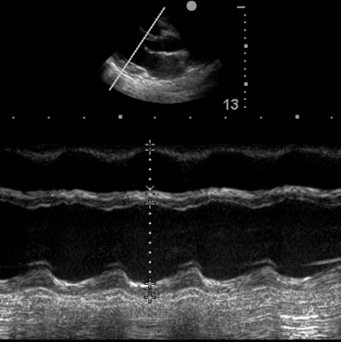

Cardiac Ultrasound

- Appropriate probe selection, gain, depth, and positioning

- Subcostal four-chamber view

- Subcostal IVC and aorta assessment

- Apical four-chamber view

- Parasternal long-axis view

- Parasternal short-axis view

- Assessment for pericardial fluid

- Qualitative ventricular function (“eyeballing”)

- Assessment of venous return and preload